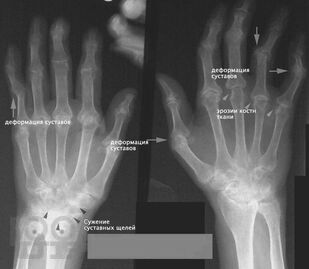

Ревматоидный артрит

Учебное пособие предназначено для студентов, обучающихся по специальностям 31.05.01 – Лечебное дело (очная форма обучения) для изучения в рамках дисциплины "Факультетская терапия, профессиональные болезни". В пособии имеются ситуационные задачи и тестовые задания, оно иллюстрировано рисунками, схемами и таблицами.